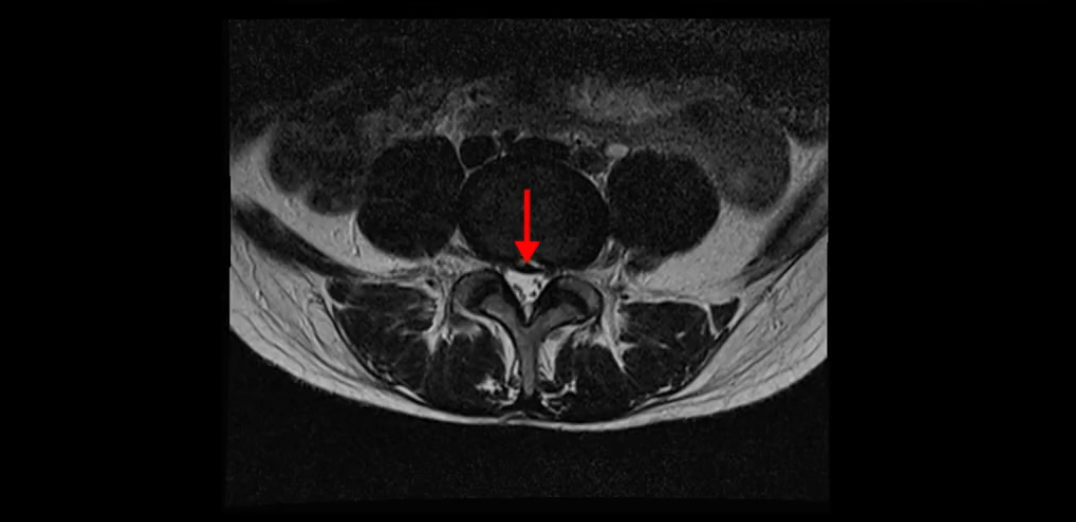

우선 이분의 MRI를 보고 먼저 설명을 드린 후 이런 환자분들의 통증의 원인은 무엇인지, 그리고 치료는 어떻게 해야 하는지 자세히 설명 드리겠습니다.

이분 MRI를 보시면 두 마디의 퇴행성디스크가 있습니다. 그리고 디스크가 조금씩 밀려 나와 있고요. 그런데 디스크 탈출 정도는 두 마디 다 심하지 않습니다. 4번 5번에는 디스크 탈출이 약간 있고,

척추관협착도 약간 진행이 되고 있고요.

5번 1번은 디스크 탈출이 가운데 쪽으로 살짝 있습니다.

또한 양쪽 신경 가지가 빠져나가는 추간공은 매우 넓은 상태입니다.

중요한 것은 이 정도 경미한 탈출과 협착으로는 양쪽 다리가 저리고 아플 수가 없습니다.

그리고 만약에 이 디스크가 급성으로 찢어진 것이라면 아주 심한 디스크성 통증이 있겠죠. 기침이나 재채기를 하면 심하게 아프고 허리를 조금만 구부려도 아주 날카로운 통증들이 생길 겁니다. 그런데 이분은 이런 증상이 전혀 아닙니다. 디스크의 돌출 정도와 협착이 전혀 심하지 않기 때문에 이분이 가지고 계신 양쪽 다리 저림, 특히 이분은 누워있을 때도 양쪽 다리가 저리다고 하는데, 디스크 때문에 그런 증상은 생길 수가 없습니다. 또 이 디스크는 오래된 디스크, 이미 찢어진 섬유륜이 아문 디스크이고, 그러니까 이분은 기침이나 재채기를 못하는 증상이 없는 거죠. 그 다음에 허리를 구부릴 때 뻐근한 증상은 있지만 아주 날카로운 통증은 없습니다.

이분 MRI를 보시면 퇴행성디스크가 있고 약간의 협착이 있지만 이 정도의 퇴행성디스크와 협착으로는 신경이 눌려서 양쪽 다리가 저리고 아픈 증상이 나올 수가 없습니다. 그래서 MRI와 이 환자분의 다리 증상이 매치가 안 된다고 하는 의사들이 많은 겁니다.